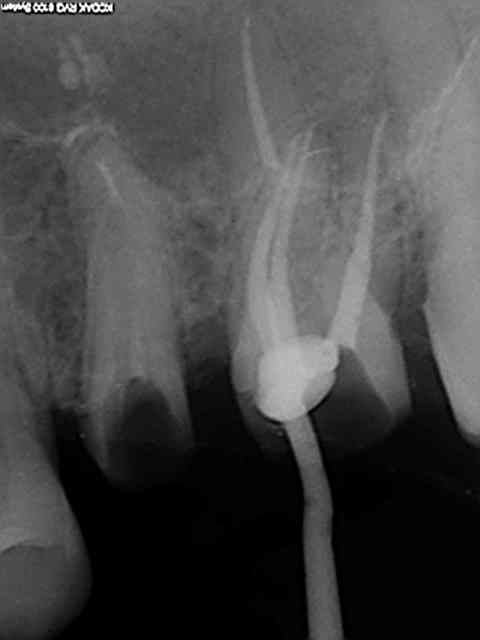

Quand je chope le mv2 qui m'avait échappé la semaine suivante.